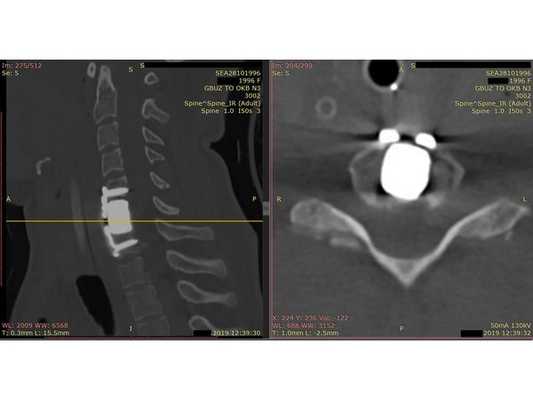

- Компьютерная томография шейного отдела позвоночника: выявлен компрессионно-оскольчатый перелом тела 6-го шейного позвонка (С6) и его дуги справа.

Контрольная КТ шейного отдела позвоночника на уровне тела позвонка С6. Виден установленный кейдж из пористого никелида титана и фиксирующая шейная пластина.

Ей рекомендовано на месяц обездвижить шейный отдел позвоночника жёстким шейным ортезом. Через месяц назначена контрольная КТ шейного отдела позвоночника и повторный осмотр.

Через месяц на КТ шейного отдела позвоночника не было отрицательной динамики. При осмотре: неврологический статус без патологии, пациентка жаловалась на лёгкую осиплость голоса.